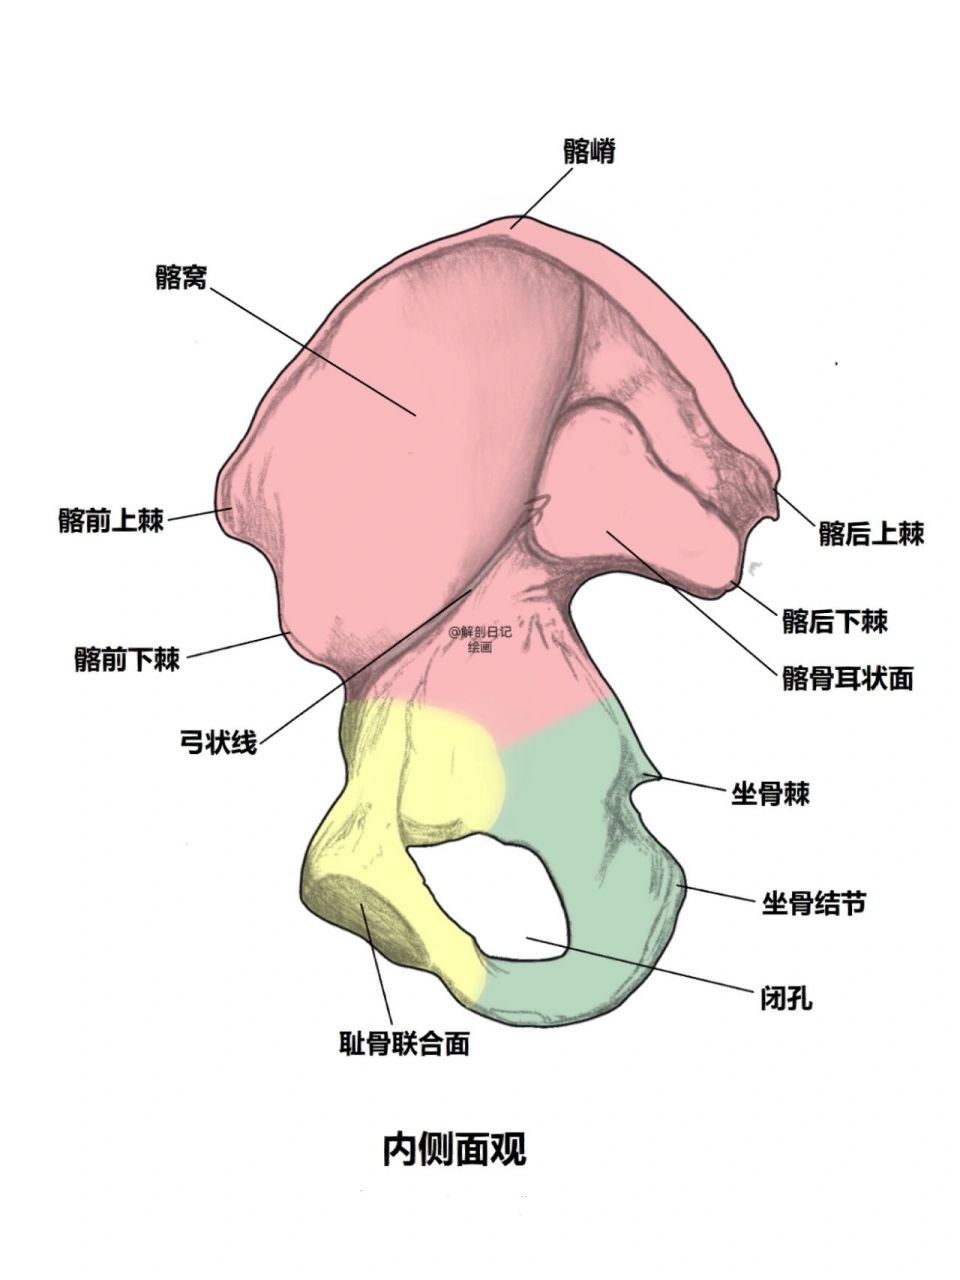

骨骼日记之髋骨 简介: 髋骨为不规则骨,由髂骨,耻

图片尺寸960x1280